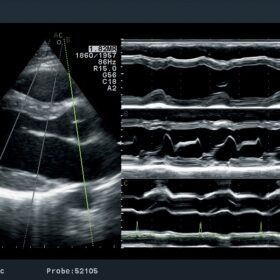

Cardiovascular

- eTRACKING (Echo Tracking)

- Arterial Stiffness

- Flow Mediated Dilatation (FMD)

- Wave Intensity (WI)

- Automated Intima-media Thickness (IMT) Measurement

- CW Doppler by the Linear Probe

- Transit Time of Vessel Flow (TVF)

- Automated Segmental Motion Analysis (A-SMA)

- Stress Echo

- TDI (Tissue Doppler Imaging) Analysis

- Free Angular M-mode (FAM)

- Asynchrony Measurement

- Patient Friendly Trans-esophageal Probes